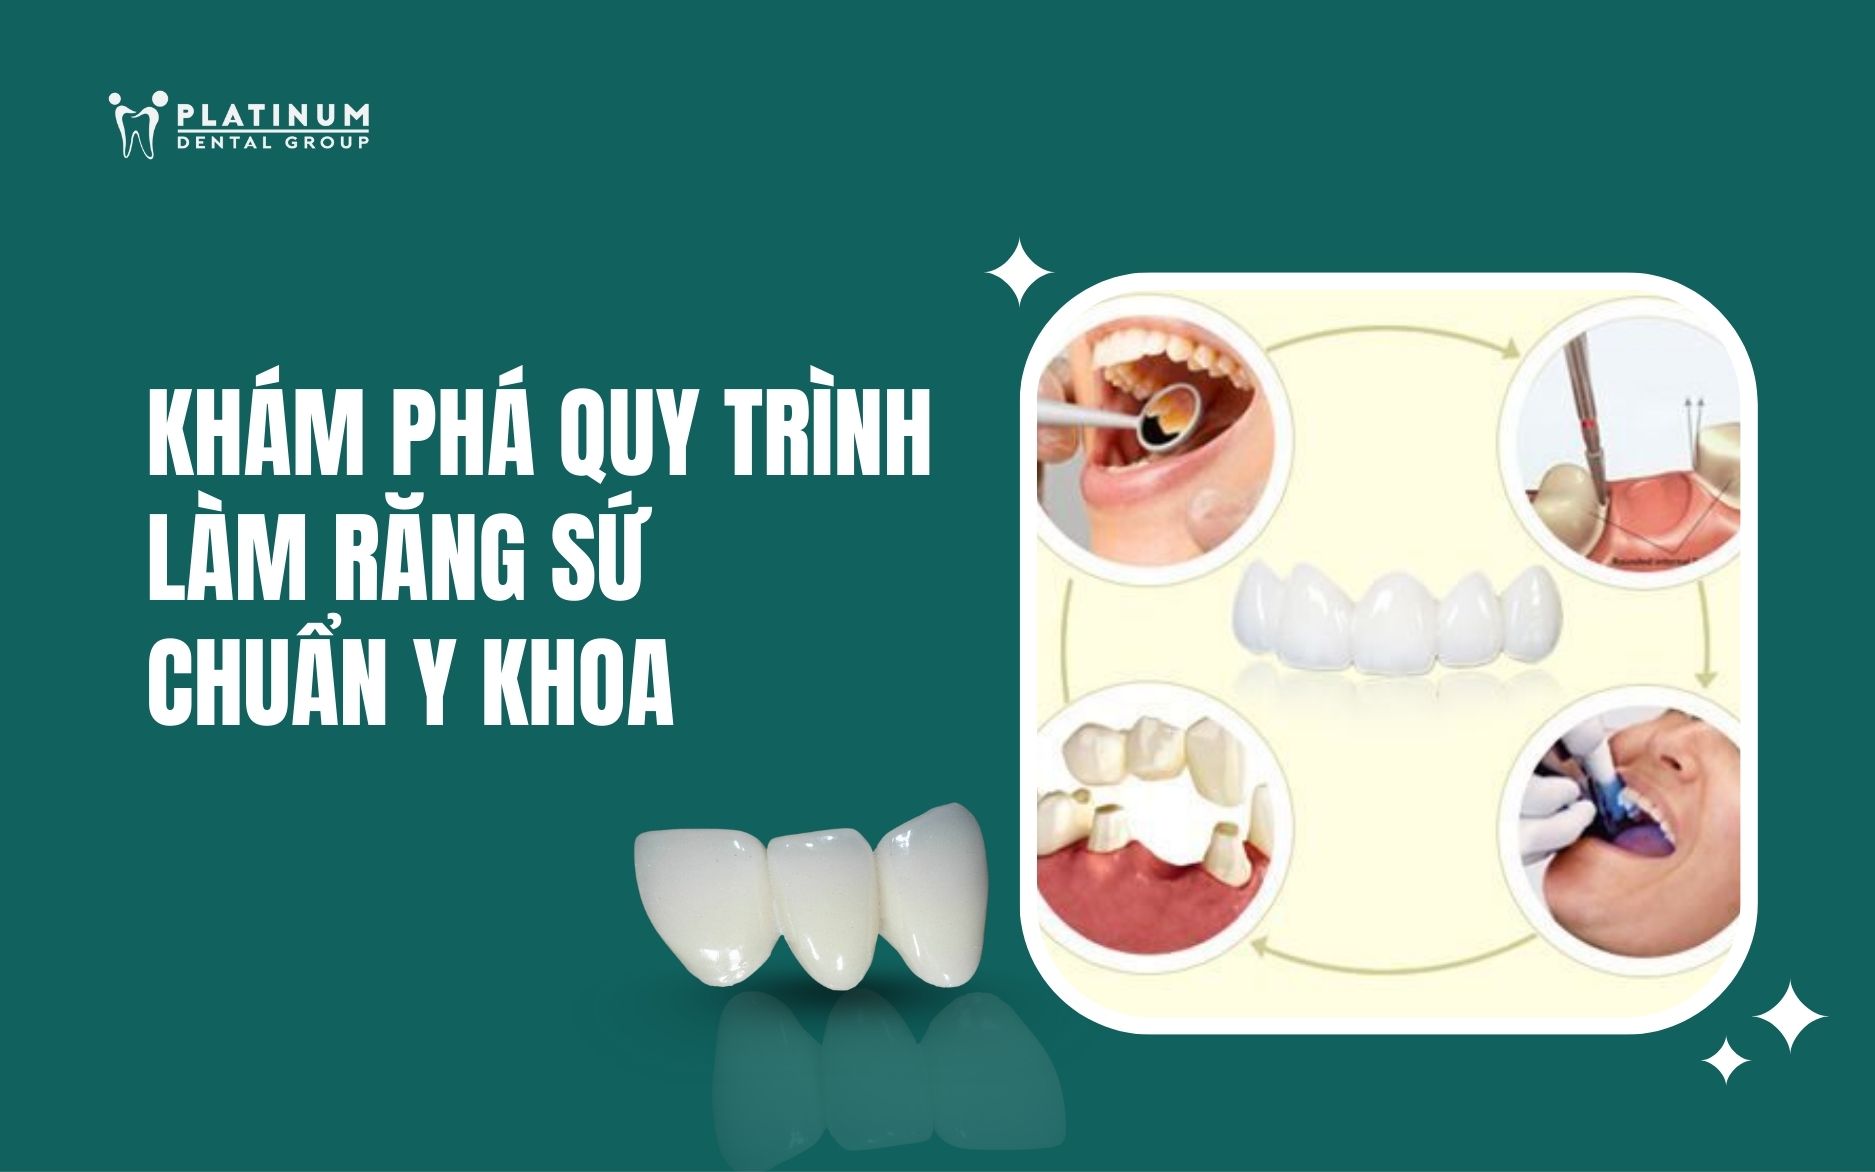

Làm sao để răng trắng sáng hơn? Dán sứ Veneer khác gì bọc răng sứ? Phương pháp nào phù hợp với bạn? Tại chuyên mục này, các bác sĩ Platinum Dental sẽ giải đáp rõ ràng, dễ hiểu mọi thắc mắc về cải thiện nụ cười, giúp bạn tự tin lựa chọn giải pháp thẩm mỹ tối ưu và phù hợp nhất với bản thân!!